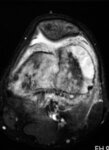

Magnetic resonance imaging, axial view; osteosarcoma of distal femur showing high-intensity signal; T2-weighted image

Personal collections of Dr Michael J. Klein and Dr Luminita Rezeanu